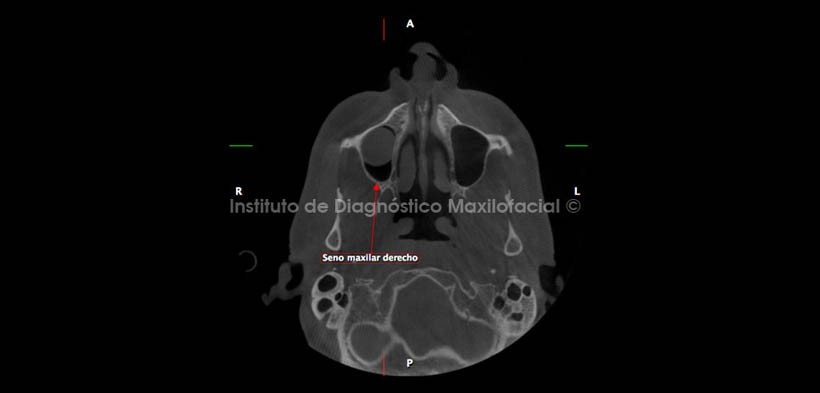

Los cortes axial, coronal y sagital; confirman la apreciación diagnóstica mencionada anteriormente ya que se evidencia la inmersión de la entidad en el seno maxilar y la relación estrecha que tiene con la pared basal; relación que es característica del Quiste Mucoso de Retención (Fig. 4, 5 y 6).

Por otro lado, se observa la estrecha relación del implante correspondiente a la región de la pieza 15 con la pared medial del seno maxilar (Fig. 7).